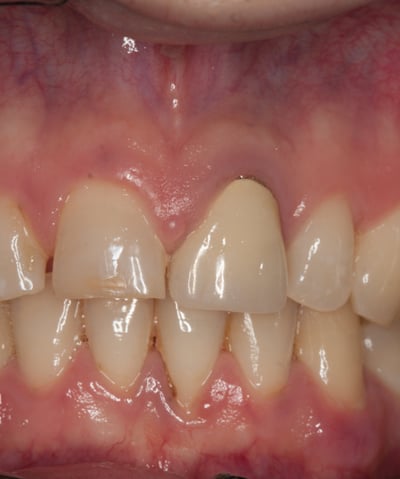

Un paziente si è presentato alla nostra attenzione con un problema di decementazione ripetuta della corona su un incisivo centrale superiore (dente 21). Oltre all'evidente instabilità protesica, la corona mostrava una discrepanza estetica marcata rispetto ai denti naturali adiacenti, compromettendo l'armonia del sorriso.

Corona incongrua: non solo non si armonizzava con i denti circostanti, ma risultava anche inadeguata dal punto di vista funzionale.

Corona Incongrua

Condizioni Iniziali